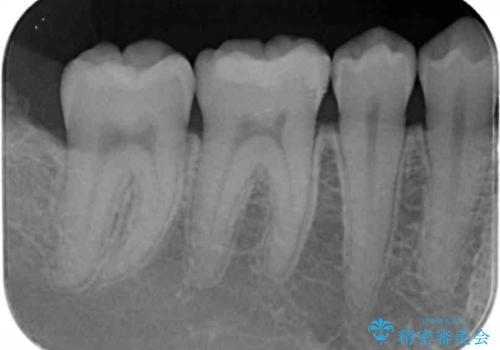

矯正後の虫歯治療 セラミックインレーでの治療

- 矯正後の虫歯治療です。

咬む面と歯と歯の間の虫歯に対してセラミックインレーでの修復処置をしていきます。

- 右下6 セラミックインレー 77,000円費用は治療当時の料金となります

下の奥歯は外から見える場所です。審美的なセラミックでの治療をおすすめします。